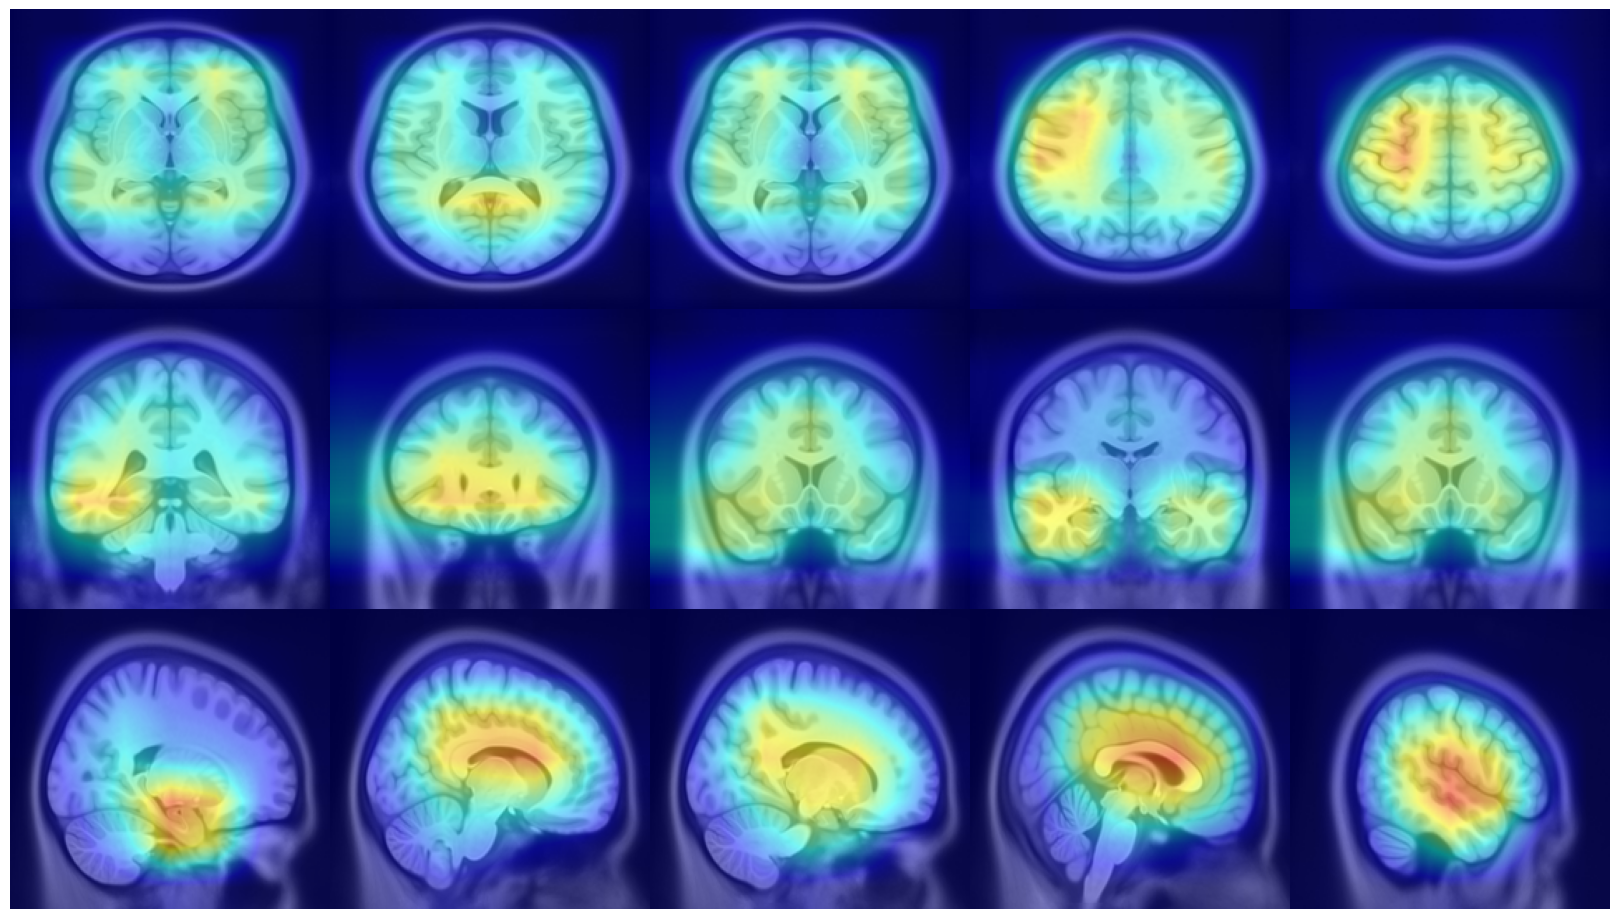

Refer to caption

Figure 7: (Left) Attention distribution for each plane averaged on all the five test to provide entire dataset distributions; (Right) Visualization of mean 3D attention map of entire dataset overlapped to MNI152 template

This subsection examines the visual results and quantitative analysis concerning the brain areas emphasized by each model. Fig. 7, on the left, displays the attentional weight distributions across the three planes, averaged over all five folds of the cross-validation. This averaging provides a comprehensive view of the data distribution across all images in the dataset. Starting from the entire dataset distributions, the 3D attentional map was created as detailed in Section 4.3. The averaged 3D map was enhanced by a factor of 10 and overlaid on the MNI152 template, which is representative of a typical patient’s brain. Combining this template with its corresponding atlas facilitates the identification of regions that, on average, received attention from the models. The right side of Fig. 7 shows the explainable MRI generated. The visual representation also indicates that the network targets the medial temporal lobe region, as suggested by the distributions. This result is confirmed by the quantitative analysis shown in Table 8, which reports the metrics for the 20 more extensive regions selected by our model and by AwareNet. As shown in Table 8(a), the three largest regions focused by our diagnosis model are the hippocampus, the parahippocampus, and the amygdala. In contrast, the 3D attentional map generated with AwareNet appears to focus on different regions. The first 3 regions highlighted are Cerebellum Gray Matter, Lateral Occipital, and Fusiform. The right part of the hippocampus appears only after them. From this result, it is also possible to note that with the same 99.9 percentile threshold for binarization, our model highlights a much more localized region. Specifically, our model selects 17 regions with a strong concentration in the top 14. On the contrary, AwareNet highlights 88 regions, 68 of which have been omitted in the Table 8.

We also examined the interpretability of the Attention Transformer model proposed in (Altay et al., 2021). For comparison, we created 2D saliency maps using the GradCAM++ algorithm (Chattopadhay et al., 2018) across all three views and all five test sets from the different folds. These maps were combined to create a unified average 3D saliency map as outlined in Section 7. This method was also applied to generate equivalent results from the saliency maps produced using our diagnostic model. As shown in Fig. 8, the 2D maps produced by our method are generally sparser compared to those from the Attention Transformer. The method introduced in (Altay et al., 2021) employs a cross-attention mechanism via a Multi-Head. Therefore, it is plausible that the Multi-Head allows to generate 2D maps that align more meaningfully within the 3D context. This finding suggests that our approach may consider less contextual information from adjacent slices unless it is particularly relevant. In contrast, the cross-attention in the Attention Transformer might enable a more cohesive representation of the entire 3D space by considering both the local features within slices and their contextual interactions. This behavior is further clarified by creating 3D maps and overlaying them on the MNI152 template, similar to the attentional maps. As illustrated in Fig. 9 on the left, the 3D maps created using our model cover a broader and less concentrated area compared to those produced by the Attention Transformer, which are shown on the right. However, similar to the 3D attentional maps, both models predominantly focus on an area surrounding the hippocampus. As detailed in Table 9, both models identify key areas, such as the hippocampus and the amygdala, as significant. However, the emphasis on other regions varies markedly between the two. In the attention transformer model, there is a noticeable focus on the inferior lateral ventricles and the parahippocampal region, areas less emphasized by our model in this case. This result indicates that the Attention Transformer using cross-attention in combination with GradCAM can produce results similar to those obtained by our method with a 3D attentional map. As seen in Tables 8(a) and 9(b), the first four areas on which our model focused with our approach are the same as those focused on by Attention Transformer with GradCAM. In contrast, our model with GradCAM shows broader involvement with regions such as the superior and middle temporal areas, which are not as prominent in the other cases.